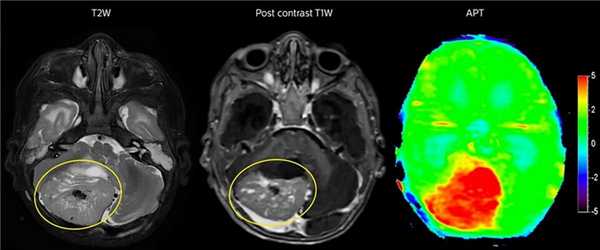

Врач выбирает метод исследования, исходя из предполагаемой патологии и того, какие есть МРТ головы:

- Обзорная МРТ. На ней видны признаки воспаления, отек, склероз, смещение структур мозга, последствия травм ушиб, некроз, кровоизлияние (за исключением первых 6 часов).

- Контрастная МРТ показывает опухоли, любые изменения сосудов, дегенеративные болезни мозга (Альцгеймера, рассеянный склероз), признаки шизофрении.

У томографа предусмотрено множество режимов сканирования – Т 1, Т 2 взвешенные, ДВИ, FLAIR, STIR. Они отражают структуры статические либо в движении. Чем больше содержится молекул воды, тем темнее цвет ткани (для Т1 взвешенных снимков). И наоборот, чем плотнее ткань, тем светлее она на снимках. Так, если в сравнении с нормой в каком-то месте есть более темный очаг, это будет свидетельствовать об отеке или выходе жидкости из сосудистого русла. Светлое пятно говорит об уплотнении тканей – склеротический, опухолевый процесс. Для Т2 режима закономерность обратная.